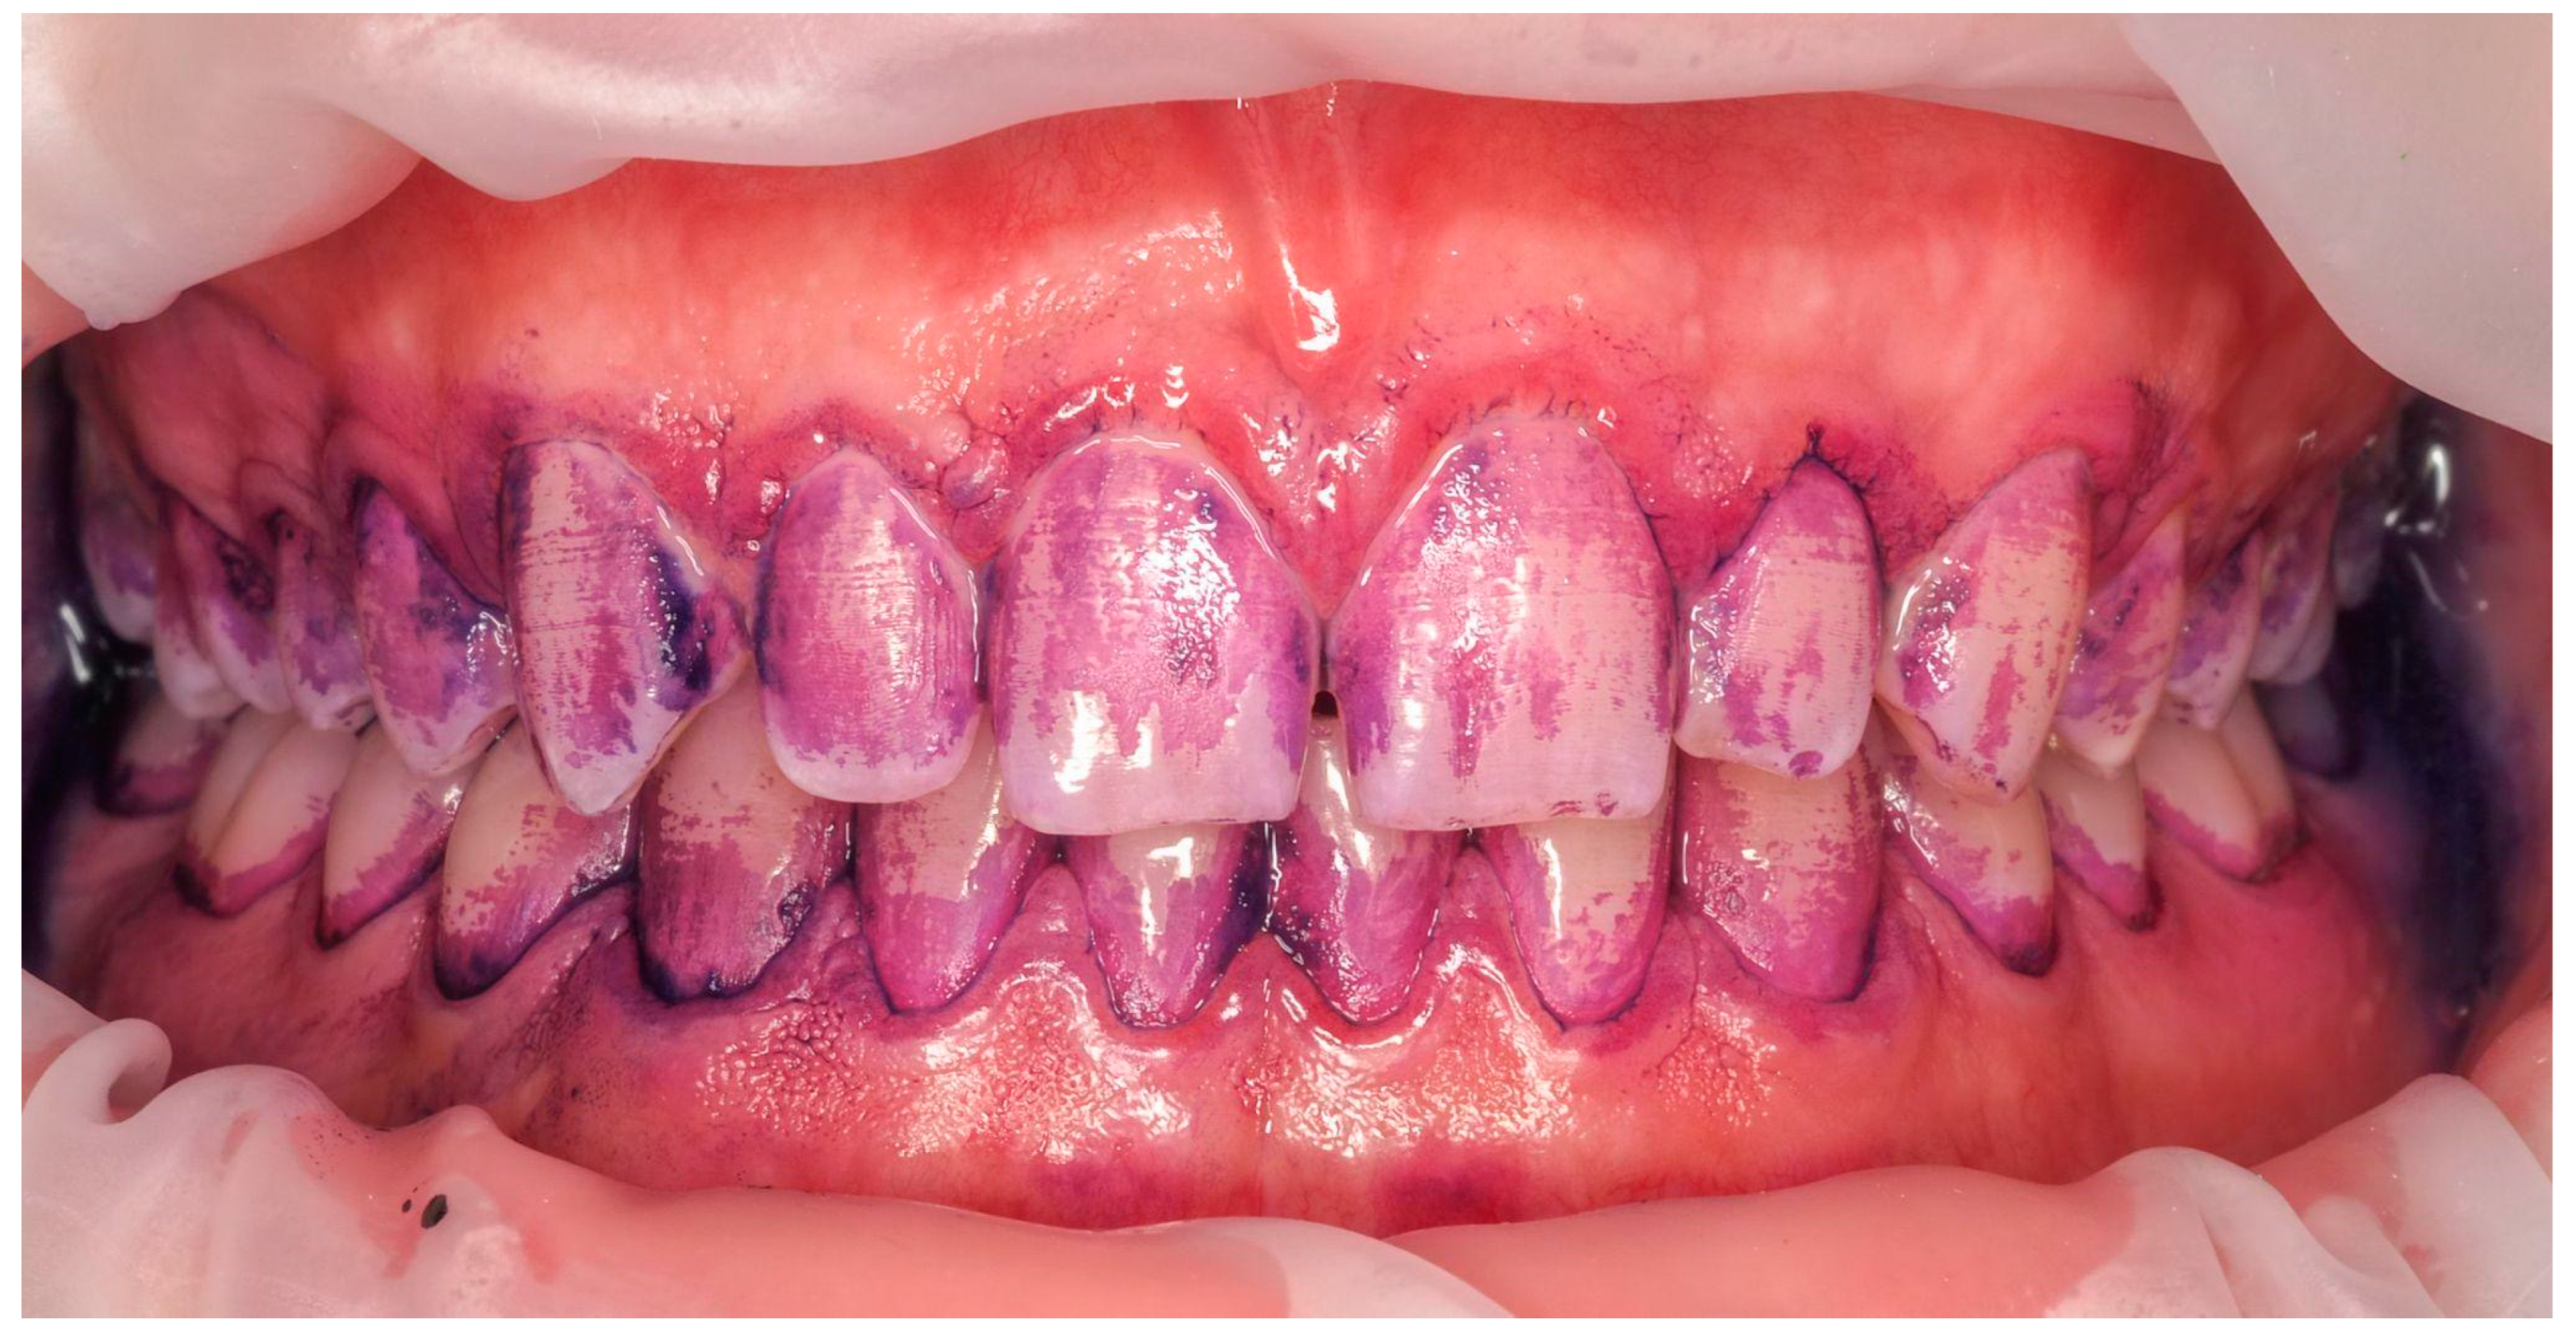

Traditional methods for removing dental deposits did not provide tools, agents, and the capability to remove biofilm, including subgingival biofilm, focusing solely on supragingival tartar. In contrast, GBT utilizes a minimally invasive, patented technology that combines the staining and removal of plaque, tartar, and deposits to effectively eliminate biofilm without damaging hard and soft tissues. This innovative approach is based on scientific findings that soft biofilm (Figure 3)—dental plaque—is the primary etiological factor in caries, gum and periodontal diseases [15,16], and also influences the progression of systemic diseases such as atherosclerosis, respiratory diseases, diabetes, and heart diseases [17].

Figure 3. Bacterial biofilm disclosed in the Guided Biofilm Therapy protocol.

Applsci 14 08159 g003